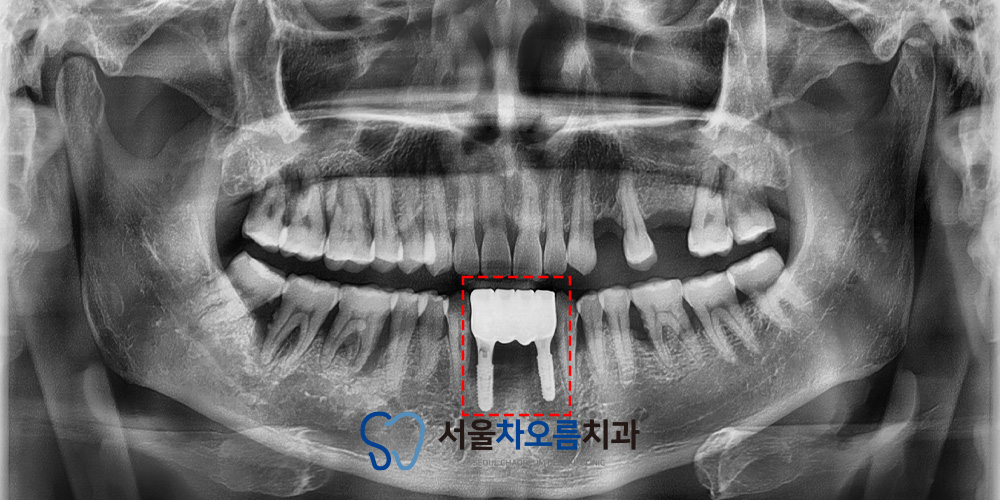

자세한 확인을 위해

파노라마를 촬영해 보니,

예상한 바와 같이 치주질환으로 인해

잇몸뼈가 소실되어 있었습니다.

주변 치아 전부 상황이 안 좋았기 때문에

브릿지를 진행하더라도

예후가 좋지 않을 가능성이 높았습니다.

브릿지는 양옆 치아를 지대치로 삼아

힘을 분산시키는 방식인데,

이미 치주질환으로 잇몸뼈가 소실되어

지지력이 떨어진 상태라면

치료 후에도 흔들림이 진행되거나,

지대치에 부담이 집중되어

문제가 반복될 수 있습니다.

그래서 병점치과 365서울차오름에서는

전반적인 치주 상태와 치조골 소실 범위를

종합적으로 고려하여,

상태가 좋지 않은 세 치아를 모두 발치한 후

임플란트를 식립해 브릿지 보철을

진행하는 방향으로 치료 계획을 세웠습니다.